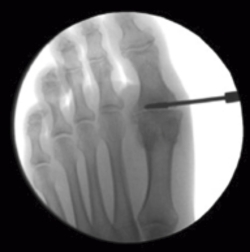

Se debe acceder a la articulación mediante 1 o 2 portales articulares situados a ambos extremos de la articulación a nivel dorsal (Figura 1). Deben ser unos portales un poco más grandes de lo normal, de 2 a 3 mm, que nos permitan un buen acceso a la articulación y poder extraer los fragmentos de cartílago que no podamos triturar. La fresa a utilizar es la Shannon® larga o Shannon® 44, que permite acceder a toda la articulación (Figura 2). En ocasiones, podemos utilizar la fresa de tipo pino (llamada así por su forma).

Figura 2. Cruentación de las superficies articulares con la fresa Shannon® bajo control radiológico.